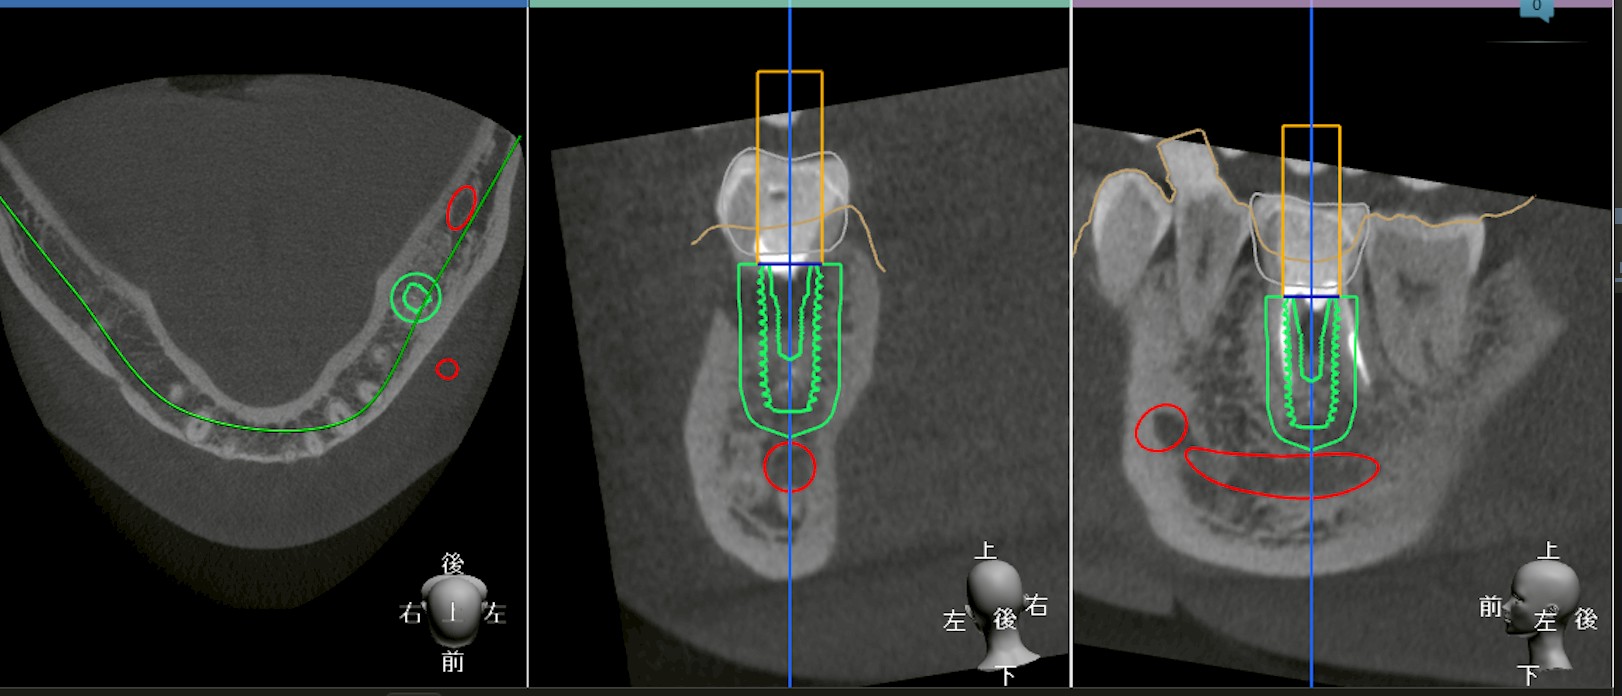

サージカルガイドとは、インプラントを埋入する位置・角度・深さを事前に設計し、その設計通りにドリリングを誘導するための装置です。

・口腔内スキャナーによる歯列データ

・CT(CBCT)による骨形態データ

これらを統合(マッチング)して、三次元的に設計します。

1. マッチング誤差のリスク

口腔内スキャンデータは歯肉上部までの情報。

CTは骨情報。

この二つを重ね合わせる際に、わずかなズレ(マッチングエラー)が生じる可能性があります。

ミクロン単位のズレが、

最終的には神経・上顎洞との距離に影響することもあります。